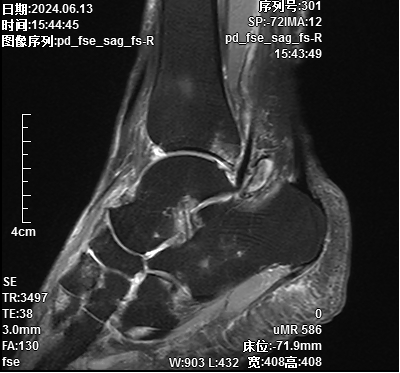

汪某,女,69岁,患者于3+月前发现右足背及右足跟腱处无明显诱因出现包块,行走时疼痛及活动受限,为求解决问题,于是来到我院骨伤科就诊。术前核磁共振提示:1.距骨前外侧、胫骨后侧多发囊肿;2.多发骨质骨髓水肿、小囊变

刘志强医生解释道,踝关节囊肿是一种多发生在肌腱旁的疾病,多因治疗后反复发作。若采取传统开放式手术,切口较大,且对周围软组织干扰严重,导致出现潜在的瘢痕疼痛及瘢痕压迫症状,且影响美观。骨伤科副主任徐驰团队根据患者病情及症状,经讨论后决定为患者行关节镜微创手术,即踝关节镜辅助下右踝关节清理+右足、踝多发囊肿切除术。在医生的细心讲解下,且汪女士既往有腰椎微创手术史,对微创手术的效果满意,于是同意了微创手术治疗。